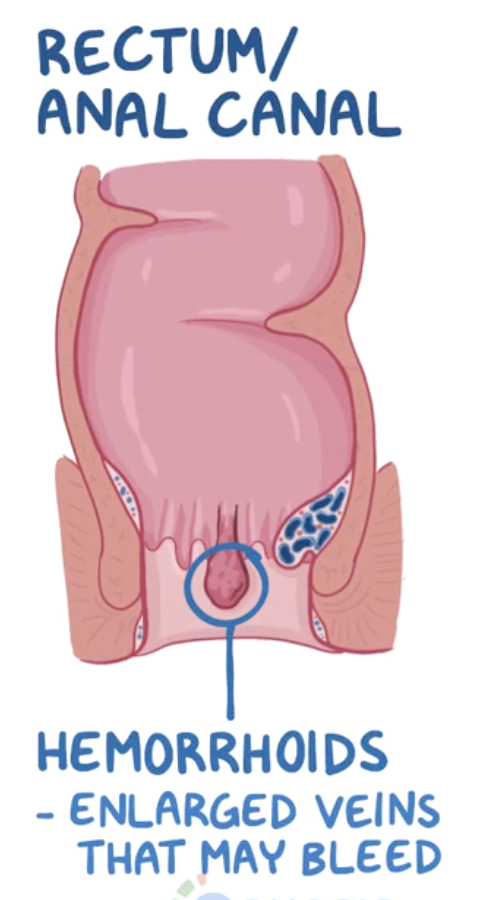

Q

If a patient develops portal hypertension (>5-10mmHg) this can cause portosystemic shunts. The 3 main places this occurs are superior portion of the anal canal, inferior portion of the esophagus and then round ligament (umbilical vein). What can portosystemic cause in the superior portion of the anal canal?

1 - fistula formation

2 - pilonidal sinus

3 - haemorrhoids

4 - diverticulitis

A

• enlarged veins that can bleed

How well did you know this?